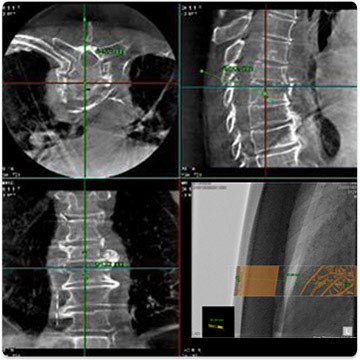

Multi Modality Fusion

Возможность наложения различных типов трехмерных КТ/МРТ и рентгеновских изображений для большей наглядности. При этом существует большой выбор настроек отображения для возможности рассмотреть различные области под различными ракурсами.

Трехмерное изображение изменяется в соответствии с изменением положения C-дуги, SID, размером поля, высотой стола и панорамированием рентгеновский ангиографии.

Возможность автоматического извлечения трехмерных данных отдельных областей (сегментация левого предсердия).

Направляющая иглы

Навигация реальном времени при введении иглы в процессе инвазивных процедур, таких как биопсия и абляция RF.

Определение оптимальной точки входа иглы и расстояния до целевой точки.

Изображения LCI и 3D-DA накладываются поверх флюороскопического изображения для визуализации анатомических структур в режиме реального времени.